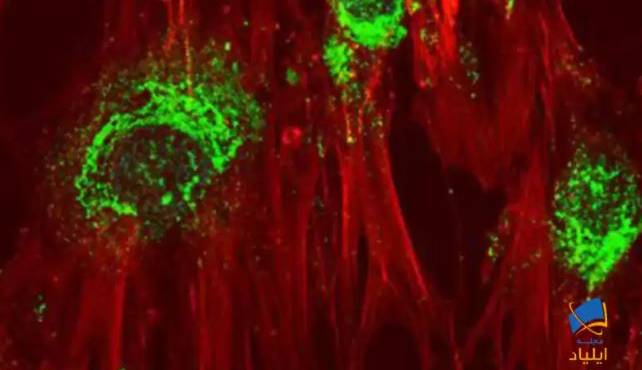

یافتههای جدید پژوهشگران برای درمان HIV از طریق سلولهای بنیادی

به نقل از ستاد توسعه علوم و فناوریهای سلولهای بنیادی؛ محققین سلولهای بنیادی اکنون راههایی [...]